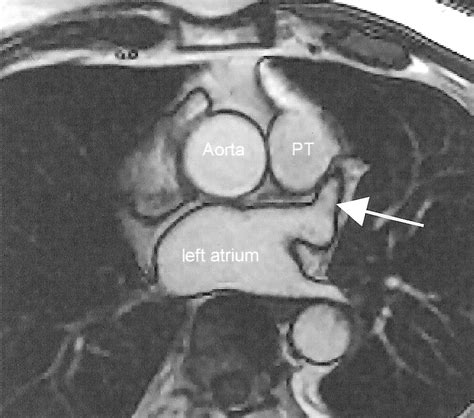

To grasp the necessity of Left Atrial Appendage Occlusion, one must first understand the anatomy and physiology of the heart in the context of AFib. The left atrial appendage (LAA) is a small, pouch-like sac located on the top of the left atrium. In a healthy heart, the atrium contracts regularly, pumping blood out efficiently. When a patient experiences atrial fibrillation, the upper chambers of the heart quiver instead of beating effectively. This quivering slows the blood flow, causing it to pool inside the LAA.

Studies have shown that in patients with non-valvular atrial fibrillation, more than 90% of stroke-causing blood clots originate in this specific area. By addressing this anatomical structure, physicians can effectively remove the "nursery" for clots without needing to systemicly thin the blood throughout the entire body.